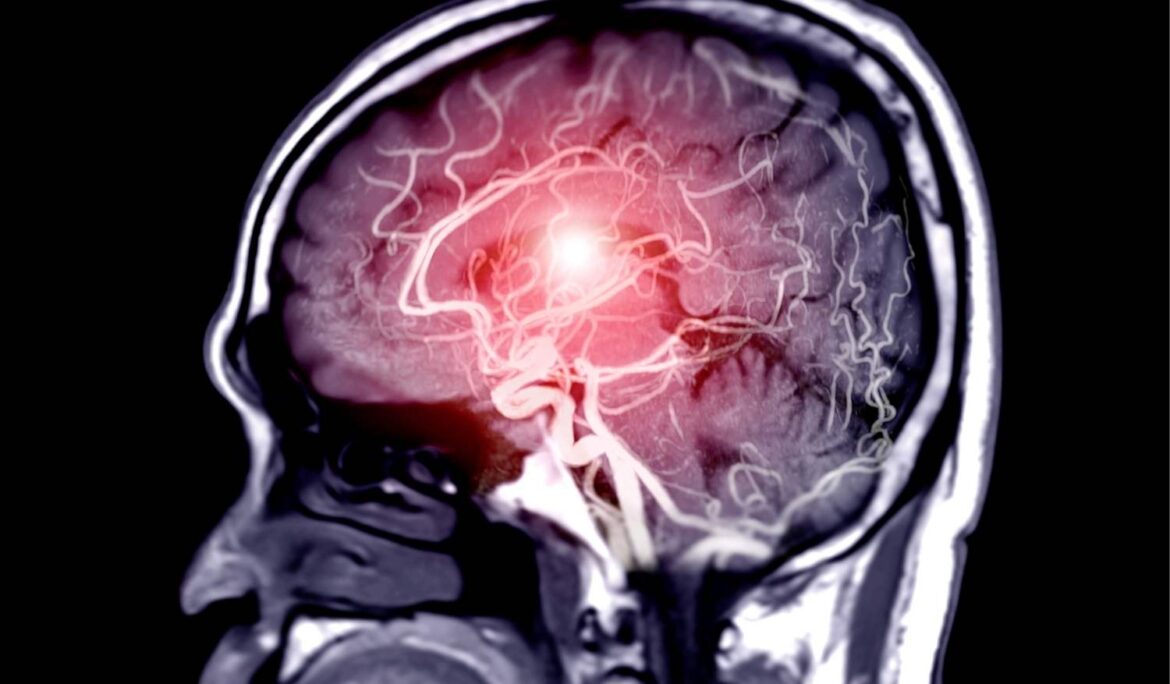

Beyin Tümörü Nedir? Beyin tümörü; beyin ve çevresindeki hücrelerin kontrolsüz bir şekilde çoğalıp büyümesi sonucu beyinde meydana gelen iyi veya kötü huylu anormal doku kitlesidir. Bebeklerden yetişkinlere